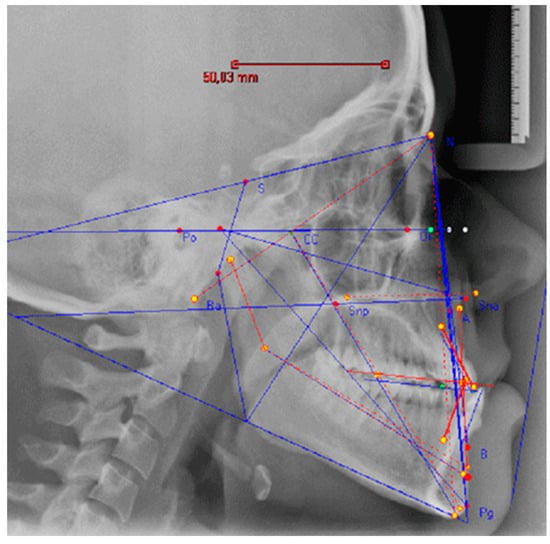

For each case, instrumental evaluations are performed: orthopanoramics (OPT), Latero-Lateral (LL) and Antero-Posterior (AP) teleradiographs, 3D Cone Beam CT (CBCT). More specifically, the CBCT scans were performed both with and without the diagnostic prostheses: this was done to allow for the 3D evaluation of the relationship between the prostheses and the skeletal bases before the surgical phase (if necessary). Lastly, a CT of the condyles in both open and closed positions was performed. VTO and cephalometric analysis are always performed before and after surgery [29,30] (Figure 3). The preliminary study and design phase was carried out digitally using 3D software (Dolphin Orthodontics software) while the fixed prosthetic rehabilitation using optical impressions (digital scanner) and CAD/CAM equipment. The surgical phase, on the other hand, was carried out according to traditional techniques.

Figure 3.

VTO and cephalometric analysis: N—nasion; S—sella; Po—porion; Or—Orbital point; CC—craniocranical point; Ba—basion; A—subspinal point; B—supramental point; Pg—pogonion. Different color lines have been used to make the image easier to read.